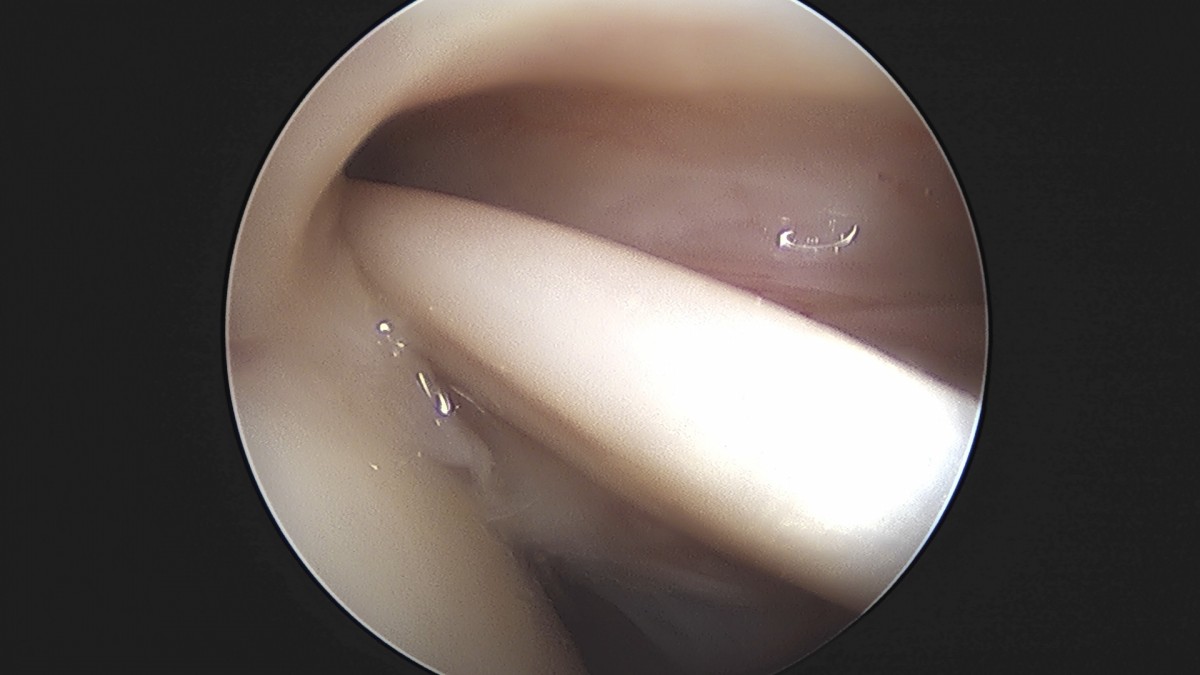

정지영원장님 어깨 관절낭 이완술 이상O 환자

작성자 최고관리자 댓글 0건 조회 743회 작성일 25-09-16 16:58